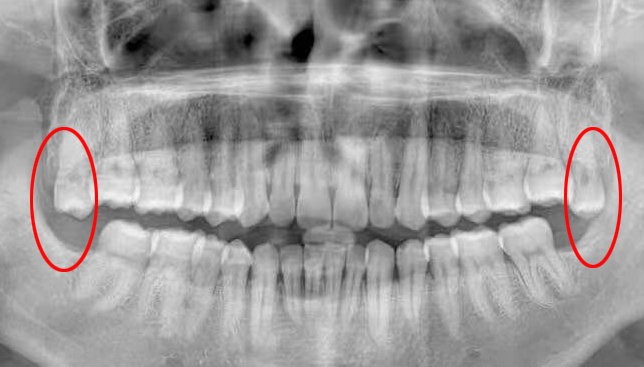

就像开头对话里提到的,智齿为了扎稳根,就会使劲顶前面的第二磨牙。如果放任不管,第二磨牙真会被顶出龋齿来,实在委屈!

这种情况如果平时没有明显症状,一般要拍片才能发现,如下图:

如果上面长了、下面没长,或者下面长了、上面没长,那长出来的那颗就会更加放肆地过度萌出。这样一来,第二磨牙会被挤得更惨,对侧的牙龈和口腔黏膜也会跟着遭殃。如下图: